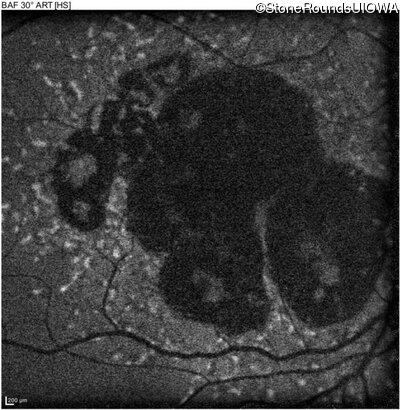

AR Stargardt Disease (IIA)

Age at visit: 59 years

This 59 year old man has noticed some blank spots near the center of his vision over the last 2 years.

Diagnosis & molecular findings

Disease Gene Allele 1 variant(s) Allele 2 variant(s) Inheritance mode

AR Stargardt Disease ABCA4 Leu2027Phe CTC>TTC IVS30+1321 A>G AR